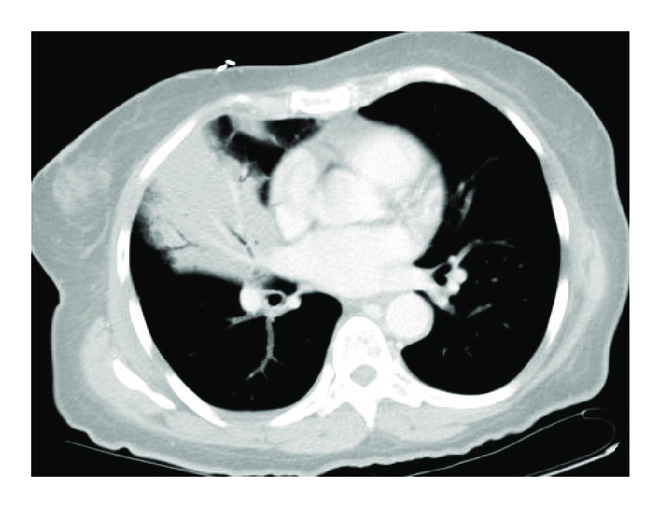

Our patient is a 59-year-old African American female with a past medical history of asthma who presented to the emergency department with shortness of breath, fever, and persistent right-sided chest pain with a cough productive of purulent sputum for the last 1 week. Physical examination was unremarkable except for crackles in the right lung base. Blood workup was significant for leukocytosis of 28,760/mm3 (4.00–11.00 K/mm3), with normal hemoglobin level, platelet count, and chemistry panel. Chest X-ray (CXR) performed was significant for a right middle lobe consolidation. A subsequent CT chest showed a right middle lobe consolidation, with an endobronchial lesion within the right bronchus intermedius, concerning for postobstructive pneumonia (Figures 1 and 2). She was started on levofloxacin for treatment and admitted for further workup.